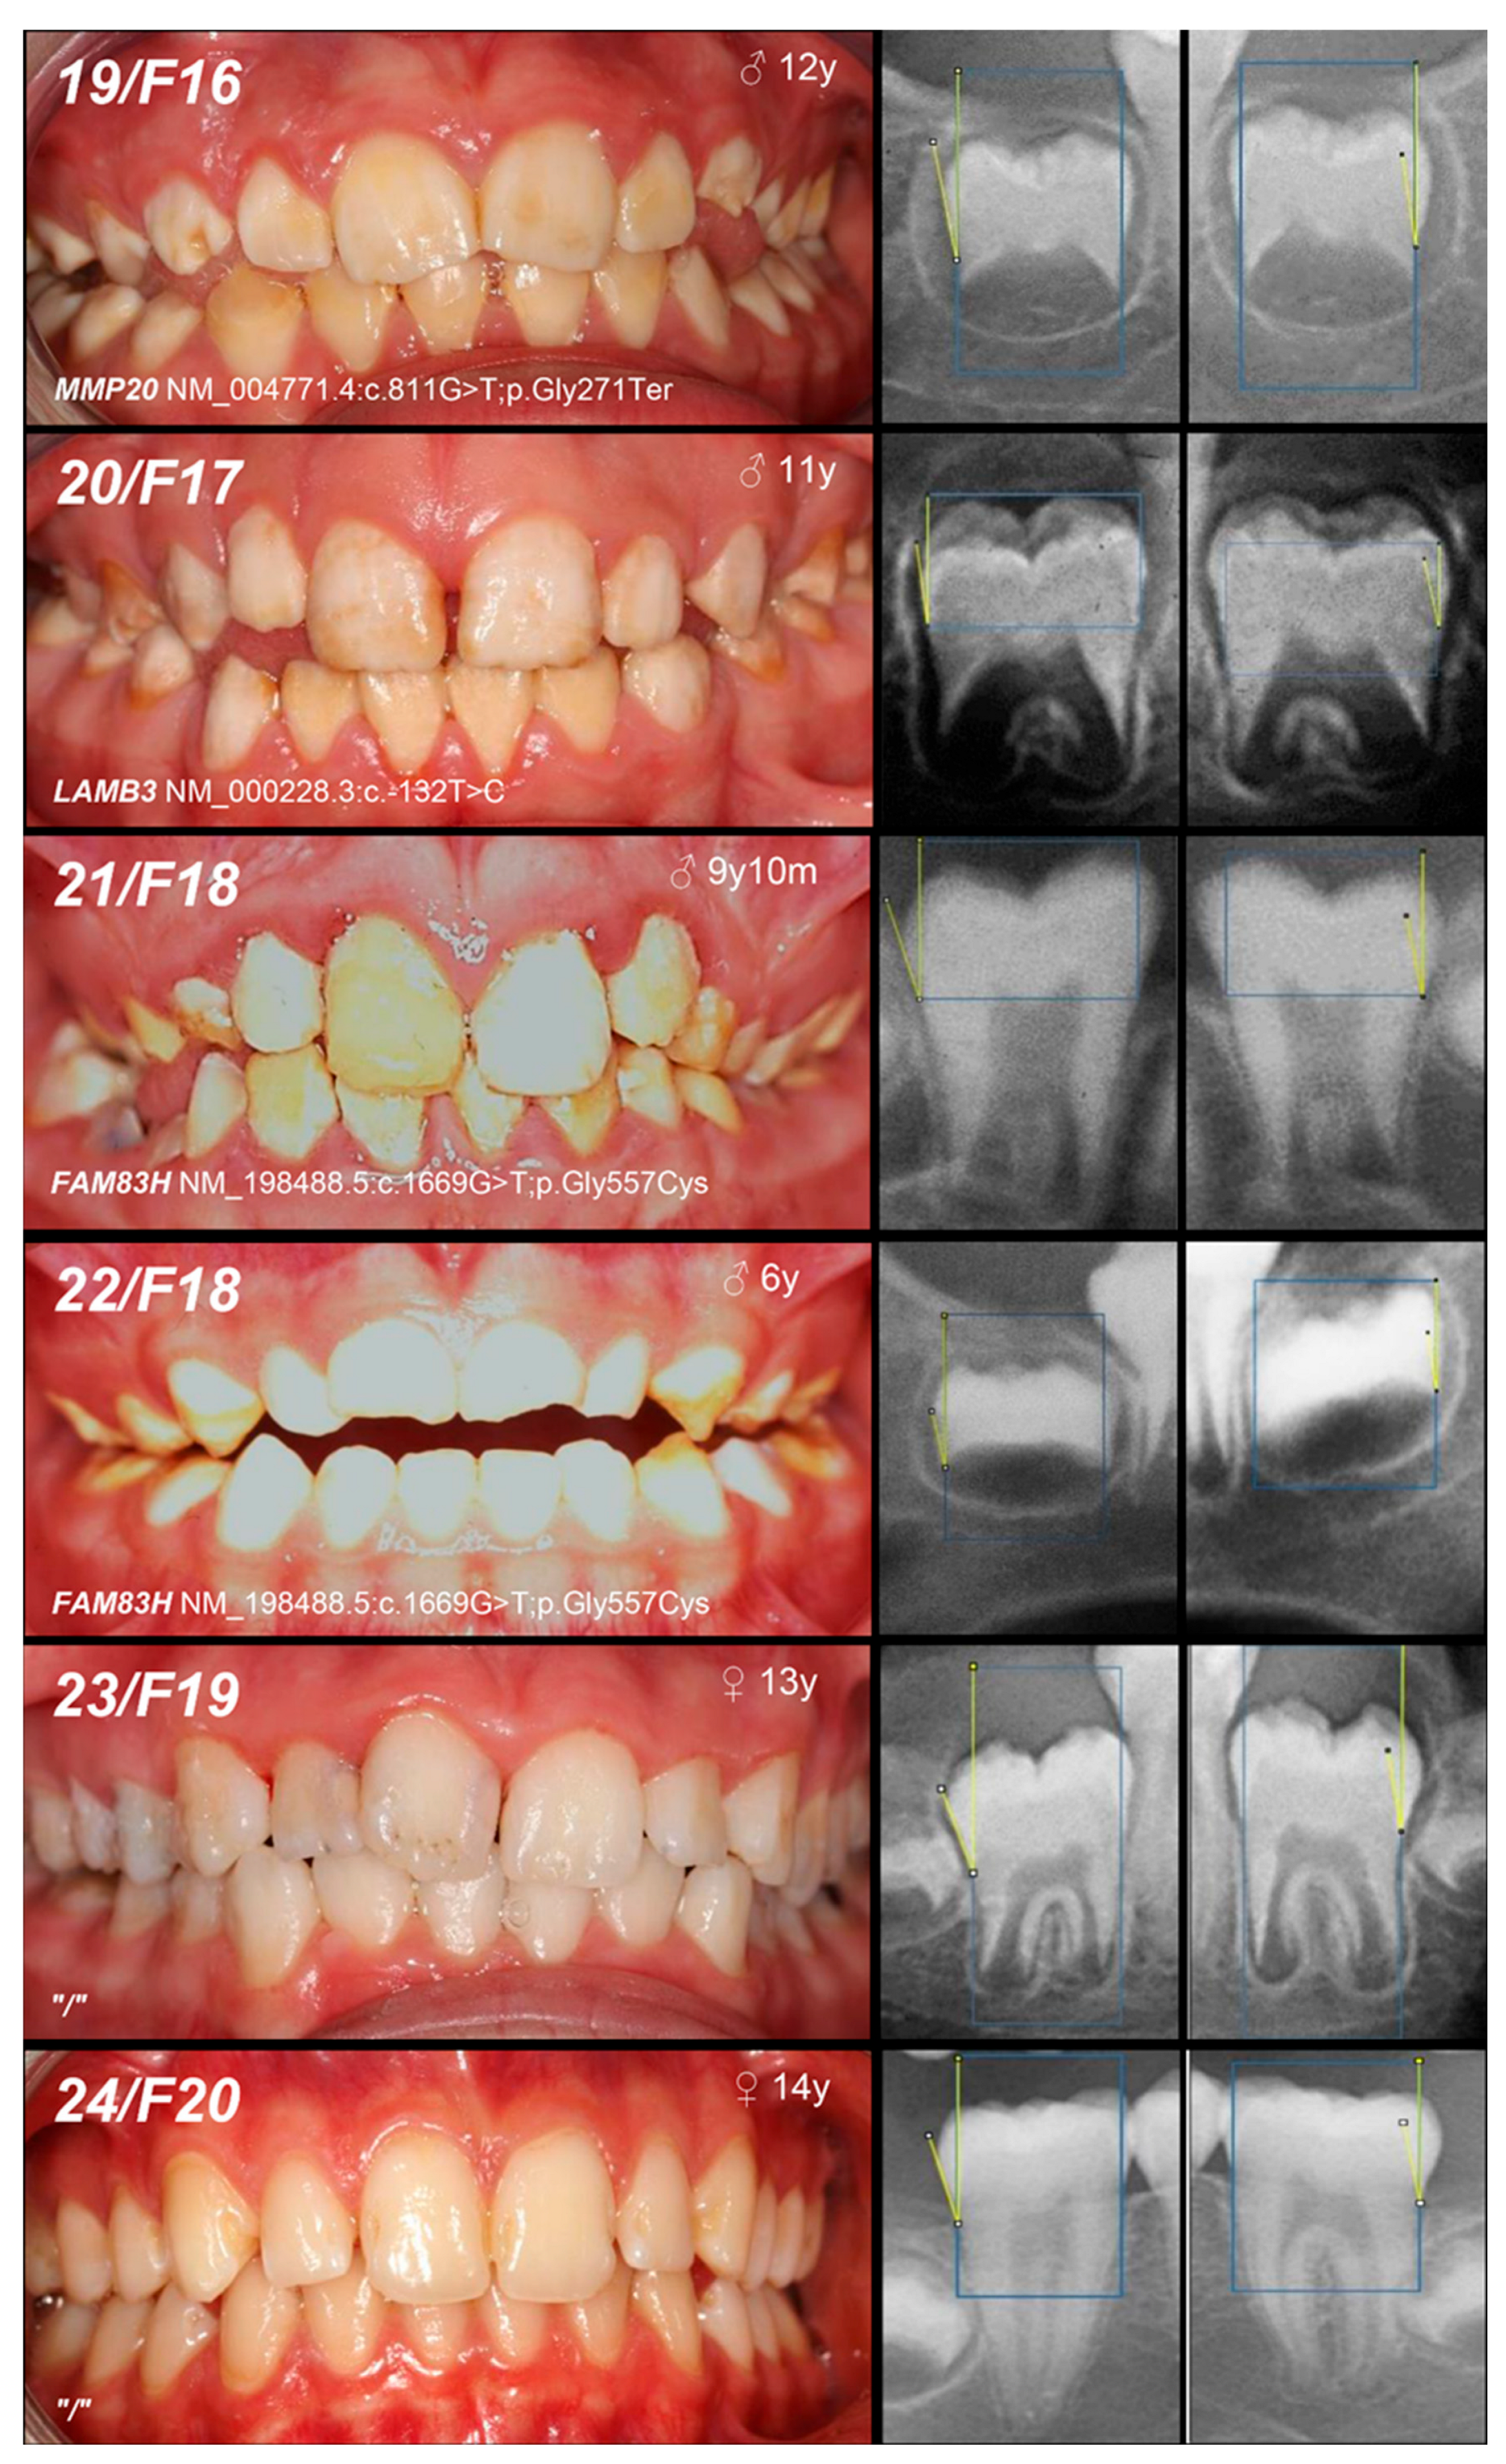

| 20, F17 | Hypoplastic (pitted) | IA, AD, LAMB3 | c.-132T>C | +/− | / | novel | Mo (AC) Fa (U) | VUS (PM2: moderate, BP7: supporting) |

| 21, 22, F18 | Hypomineralized (hypocalcified) | IIIA, AD, FAM83H | c.1669G>T | +/− | p.Gly557Cys | [29] | MoFa (NA) | benign (BA1: stand-alone, BS1: strong, BS2: supporting, BP4: supporting, BP6: supporting) * |

| +/− |